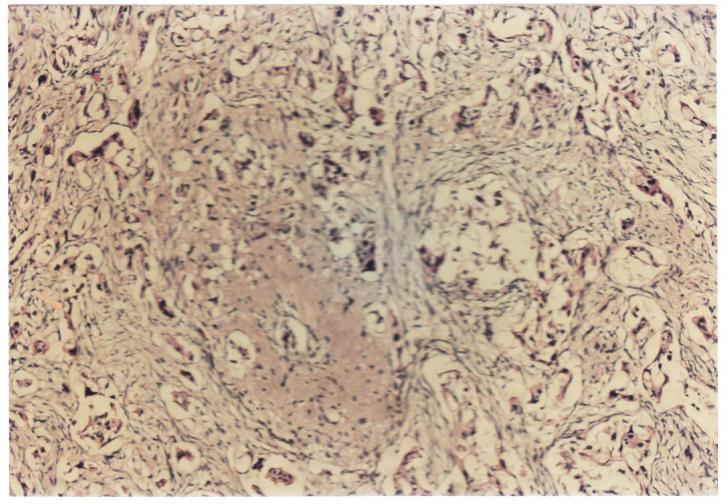

Criterii microscopice de diagnosticare a cancerului mamar

Criterii microscopice de diagnosticare a cancerului mamar Investigarea citologica a proliferarii maligne se realizeaza prin tehnica citologiei exfoliative sau a citologiei prin punctie aspirativa cu ac fin. Prima tehnica se foCiteste tot ... 703 cuvinte